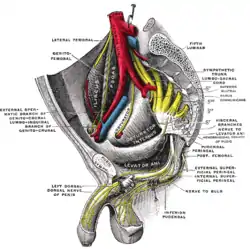

The arteries of the pelvis. Dissection of side wall of pelvis showing sacral and pudendal plexuses.

Dissection of side wall of pelvis showing sacral and pudendal plexuses. Sacral plexus of the right side.